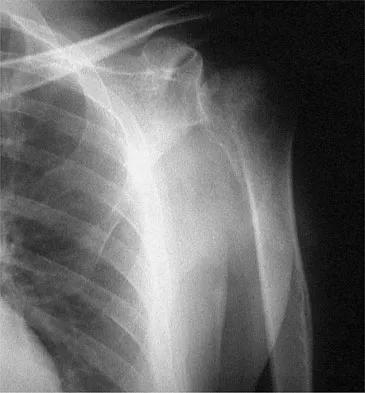

Figures 32a and 32b show the radiographs of a 13-year-old right hand-dominant boy who sustained a closed Salter-Harris type II fracture of the proximal humerus during a hockey game. The shoulder has significant swelling, but is neurovascularly intact. What treatment offers the best chance of reestablishing normal shoulder motion?

Explanation